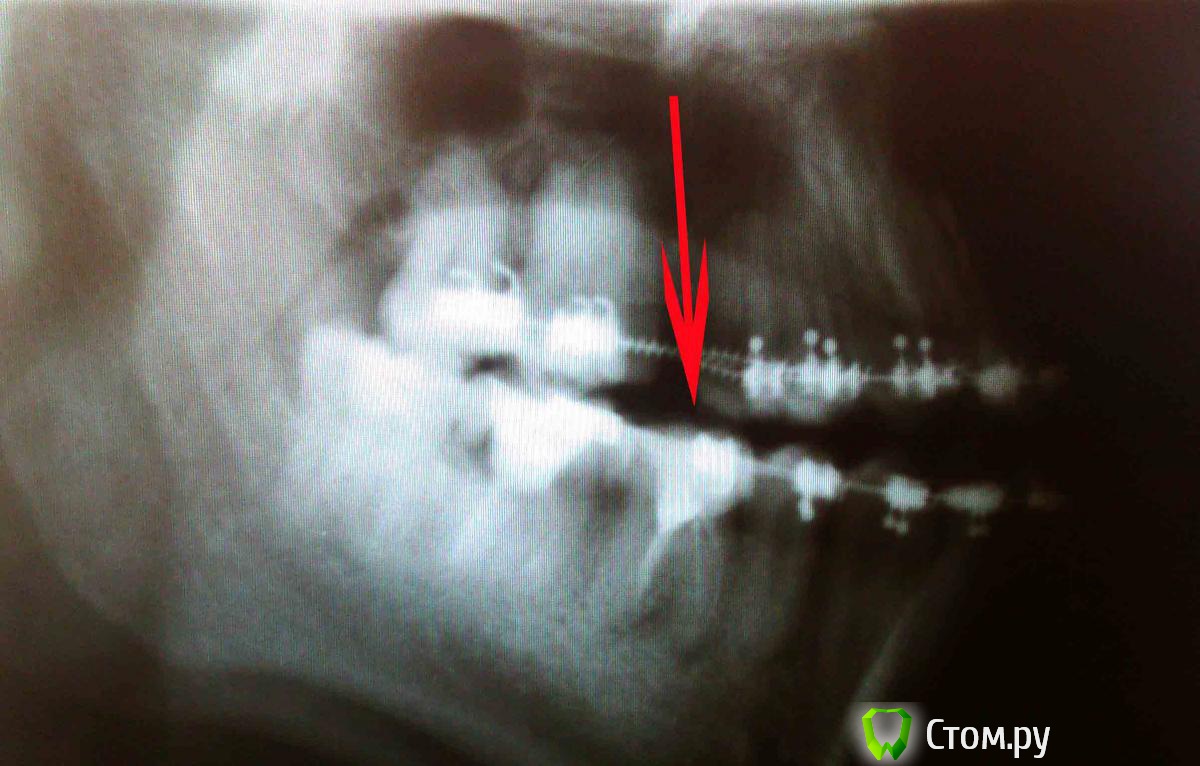

Nicholas Опубликовано 13 ноября, 2014 Поделиться Опубликовано 13 ноября, 2014 Через неделю после установки новой дуги зубы на нижней челюсти начали смещаться во внутрь один единственный зуб с пломбой на правой стороне начал болеть на прикус, не обратил внимания сразу т.к. зубы часто побаливают под воздействием дуги. Прошло 2 дня, сегодня утром проснулся и обнаружил что десна и щека припухли. Уважаемые, я нахожусь в деревне, у меня нет возможности сделать снимки, т.к. здесь нет оборудования, все, что удалось сделать прикрепил, поймите пожалуйста! И не надо называть снимки полуфабрикатами и прочими не хорошими словами! Чем богаты тем и рады... ((( В город сейчас выехать не могу, единственно, что мне доступно это антибиотики и док с древним оборудование с помощью которого единственное,что он может сделать это открыть зуб рассверливая его настолько, что стенки получаются тонюсенькими... Что мне делать, если мне вскроют зуб как поведут себя брекеты, не сломают ли они стенку зуба???Либо упорно кушать антибиотики в надежде что отек не пойдет дальше, а тем временем добираться до города?? Ссылка на комментарий

red_butler Опубликовано 13 ноября, 2014 Поделиться Опубликовано 13 ноября, 2014 требуется повторное лечение корневых каналов в зубах 4.6 4.7Ищите стоматолога-эндодонтиста Ссылка на комментарий

red_butler Опубликовано 14 ноября, 2014 Поделиться Опубликовано 14 ноября, 2014 Сейчас нужно приостановить Ортодонтическое лечение и решать проблему с зубом 1 Ссылка на комментарий